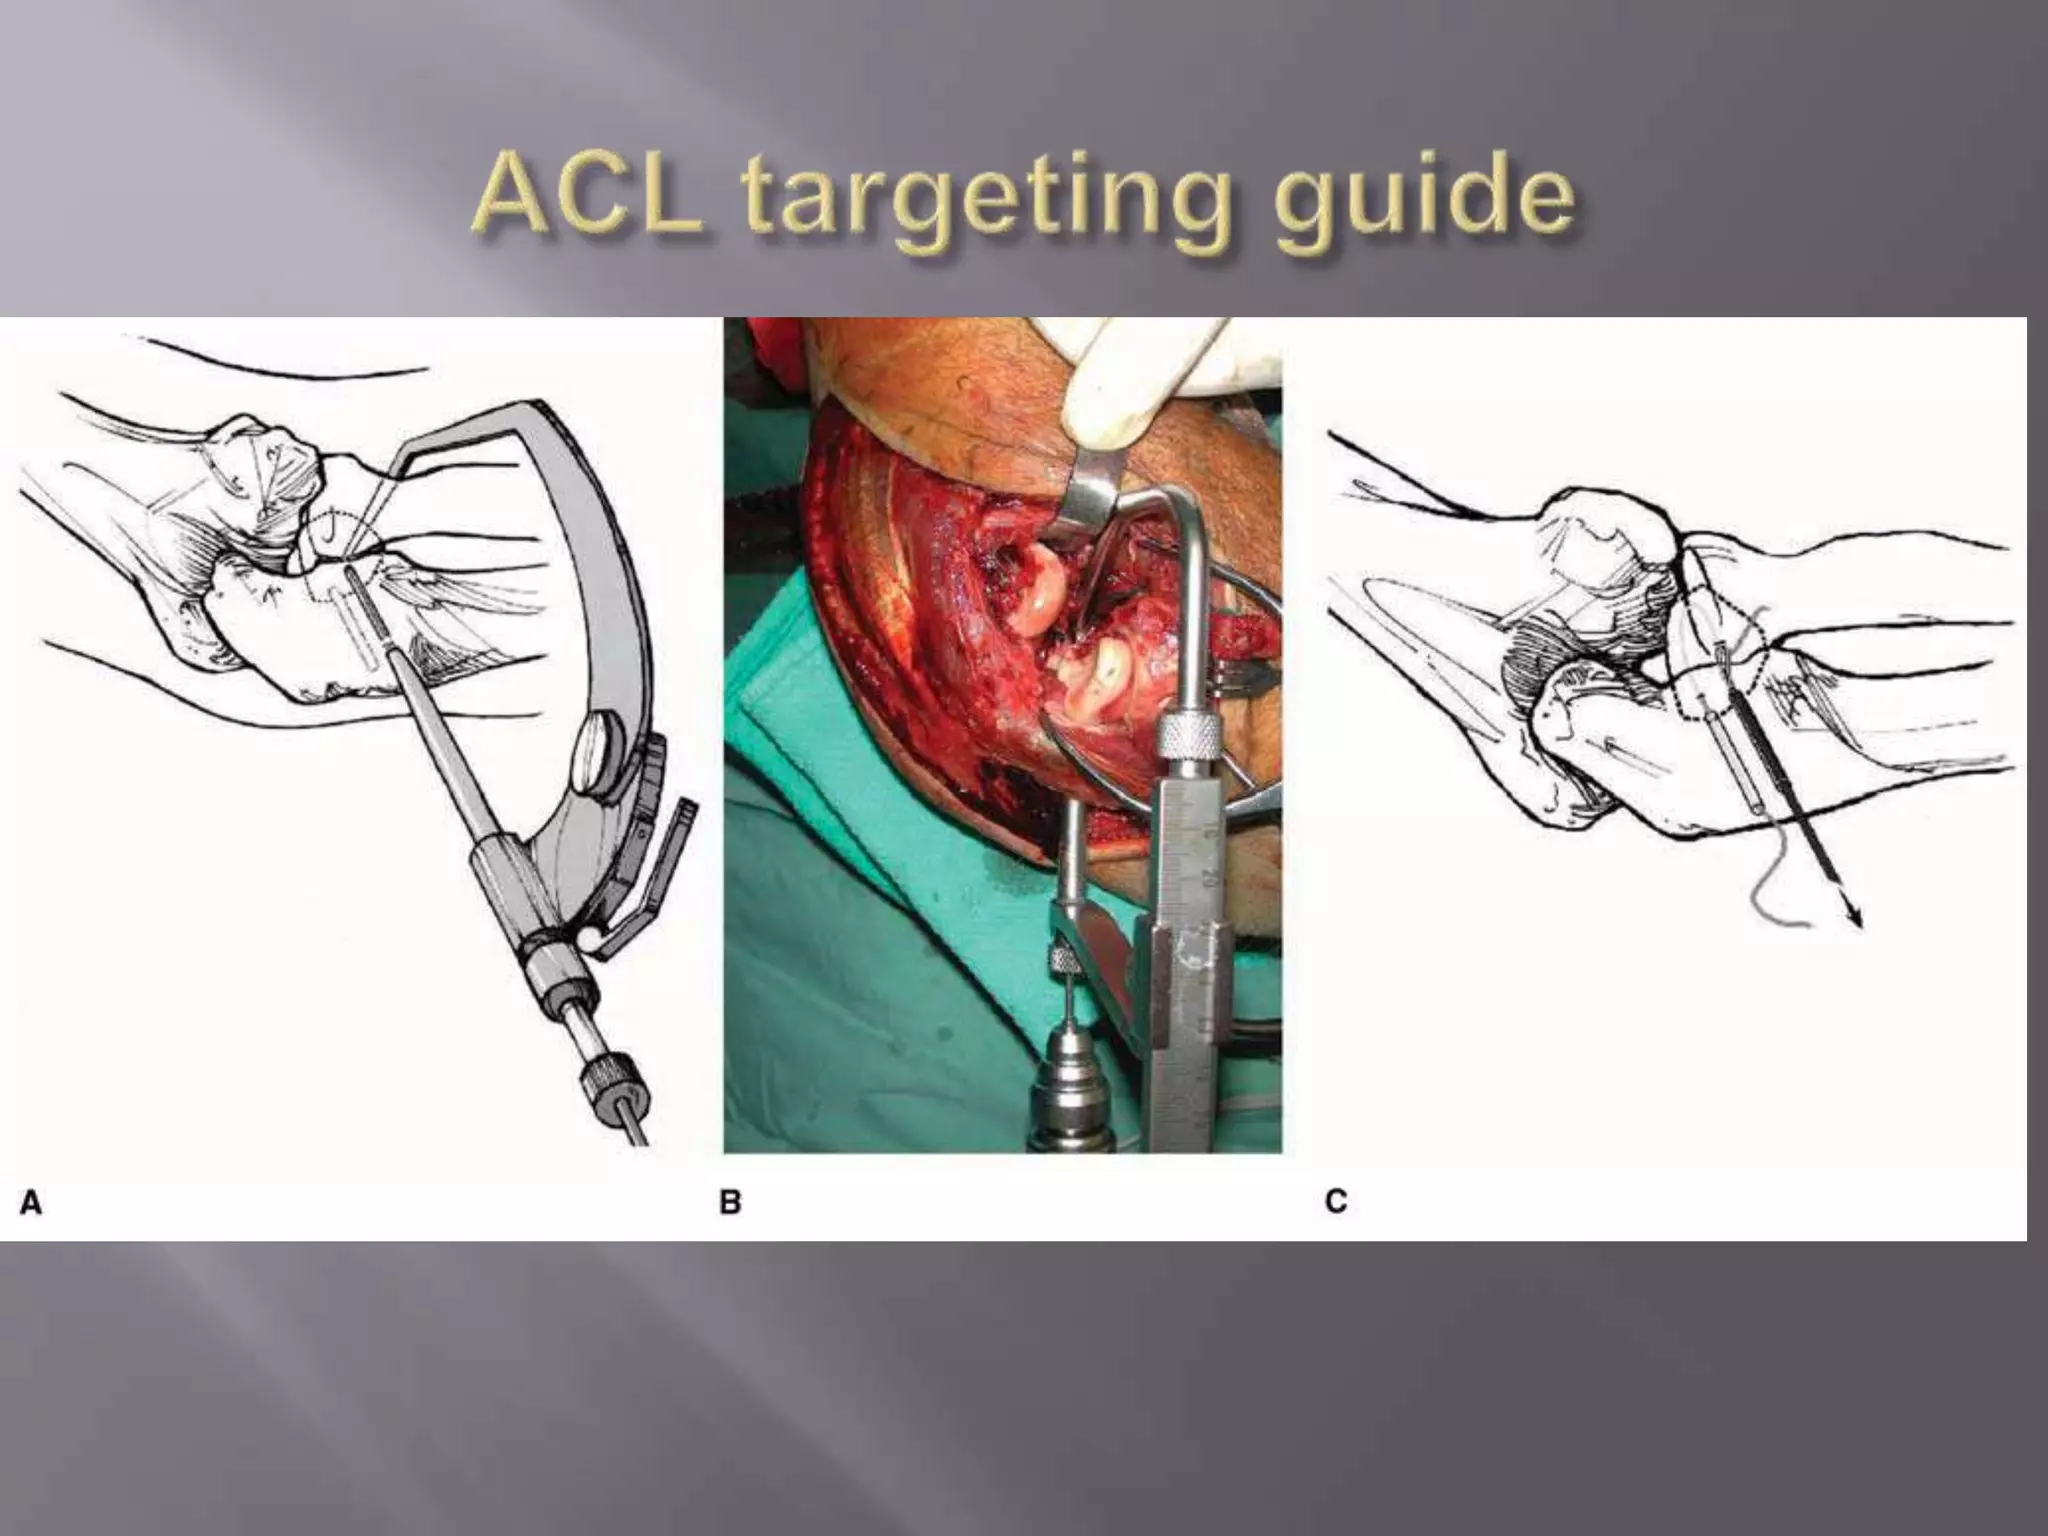

This document discusses the terrible triad injury of the elbow, which involves fractures of the radial head, coronoid process, and posterolateral dislocation. It notes the poor outcomes associated with this injury like stiffness, instability, and hardware failure. The document outlines the relevant anatomy of the medial collateral ligament and lateral uncular collateral ligament. It describes the mechanism of injury, known as the fall on an outstretched hand, and how the ligaments and capsule fail in this injury. Diagnostic imaging and classification of radial head and coronoid fractures are covered. Treatment options including observation, resection, open reduction internal fixation, and replacement are presented. Surgical approaches and techniques are also outlined.